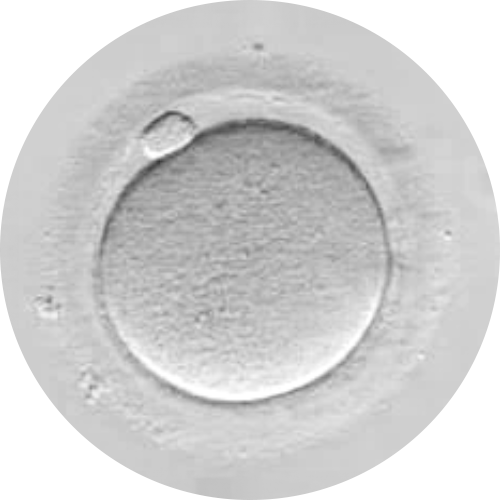

POOR OOCYTE QUALITY

RESTORED EGG

2. Differences Between Restored & Non-Restored Eggs

The eggs provide the acrosomal spindle responsible for dividing the genetic material after fertilization.

With IVF MORE®:

- The egg’s metabolism is restored and the cytoskeleton is reorganized.

- This improves the formation of the acrosomal spindle, supporting accurate genetic division.

- The result is a higher number of viable embryos and a lower rate of genetic abnormalities.